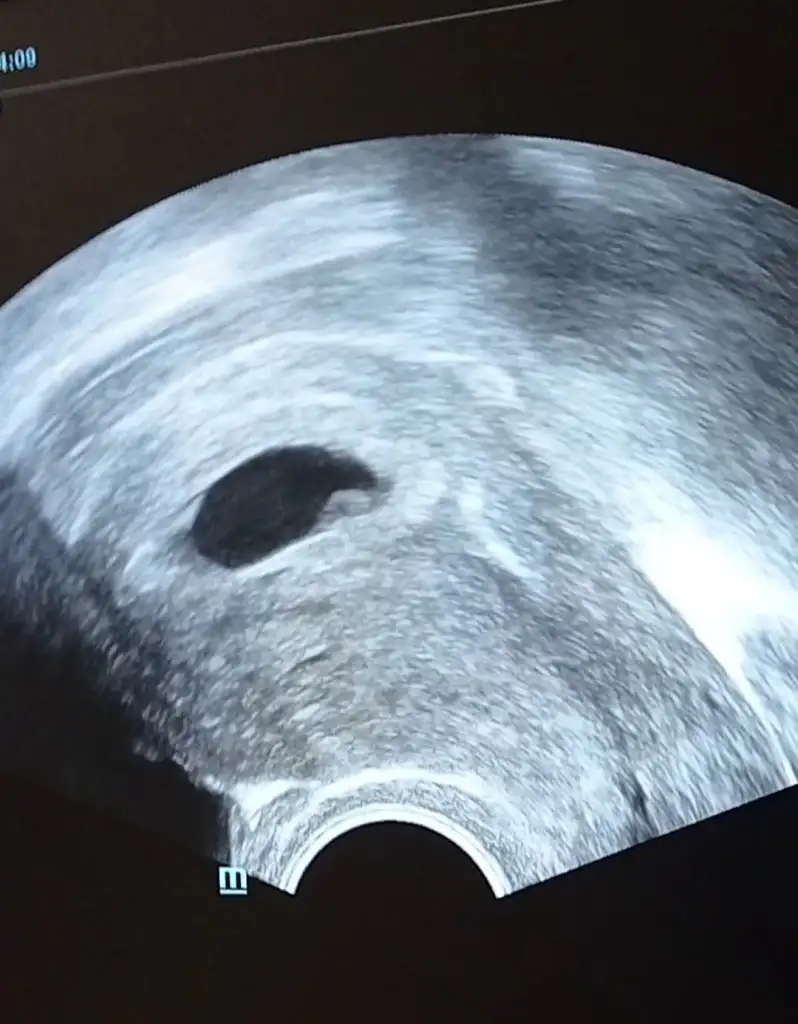

Kız görünüyorIkra meyra merhaba 6.haftamda (resme ekledim) vajinal ultrason erkek gibi demiştiniz şuan 11 hafta olduk tekrar var mı bir tahmininiz (karından ultrason )

Benimkine bakabildiniz mi acabaIkra meyra merhabalar, 12+2 haftalık görüntü. Tahminde bulunabilir misin?